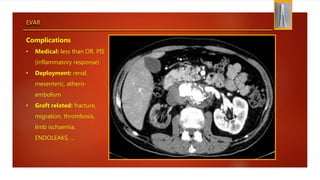

EVAR

Complications

• Medical: less than OR, PIS

(inflammatory response)

• Deployment: renal,

mesenteric, athero-

embolism

• Graft related: fracture,

migration, thrombosis,

limb ischaemia,

ENDOLEAKS, …